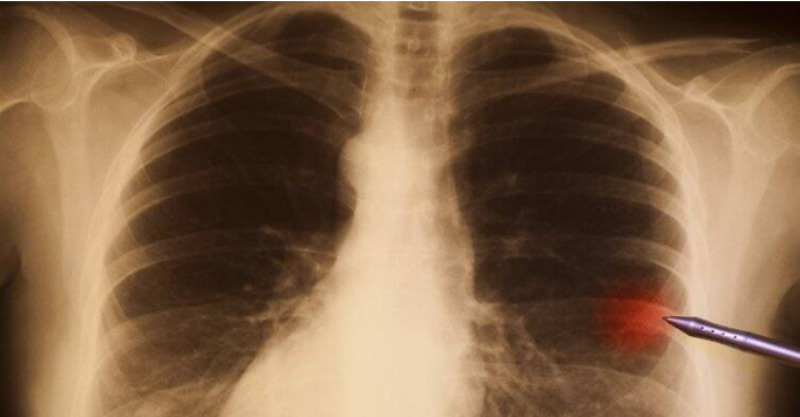

根據《中華腫瘤雜誌》刊登的一項研究指出,長期處於高壓、失眠、焦慮等應激狀態下,會導致身體的免疫系統功能下降,自然殺傷細胞(NK細胞)活性降低,這類細胞本是清除體內異常細胞的「守門員」。

一旦這些衛士「打瞌睡」,體內原本可以被清除的小異常,就可能悄悄積累,最後釀成大禍。